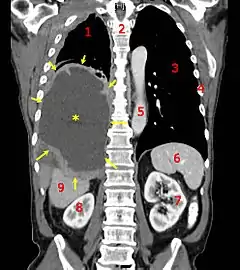

![]() A coronal سیتی اسکن showing a malignant مزوتلیوما, indicated by the asterisk and the arrows | |